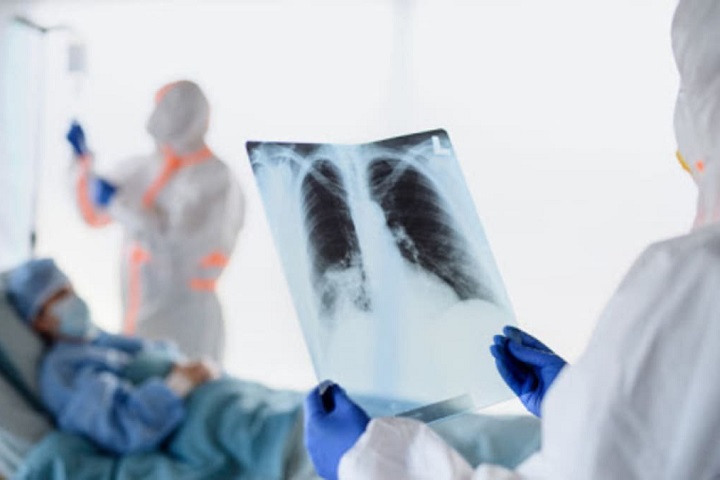

В Казахстане за сутки зафиксировано 179 случаев пневмонии с признаками коронавируса

За прошедшие сутки зафиксированы 179 случаев заболевания пневмонией с признаками коронавирусной инфекции, 3 летальных исхода и 65 человек выздоровели. Об этом сообщает Optimism.kz со ссылкой на coronavirus2020.kz.

Всего с 1 августа зарегистрировано 39724 заболевших, 415 летальных случаев, 29416 выздоровевших.